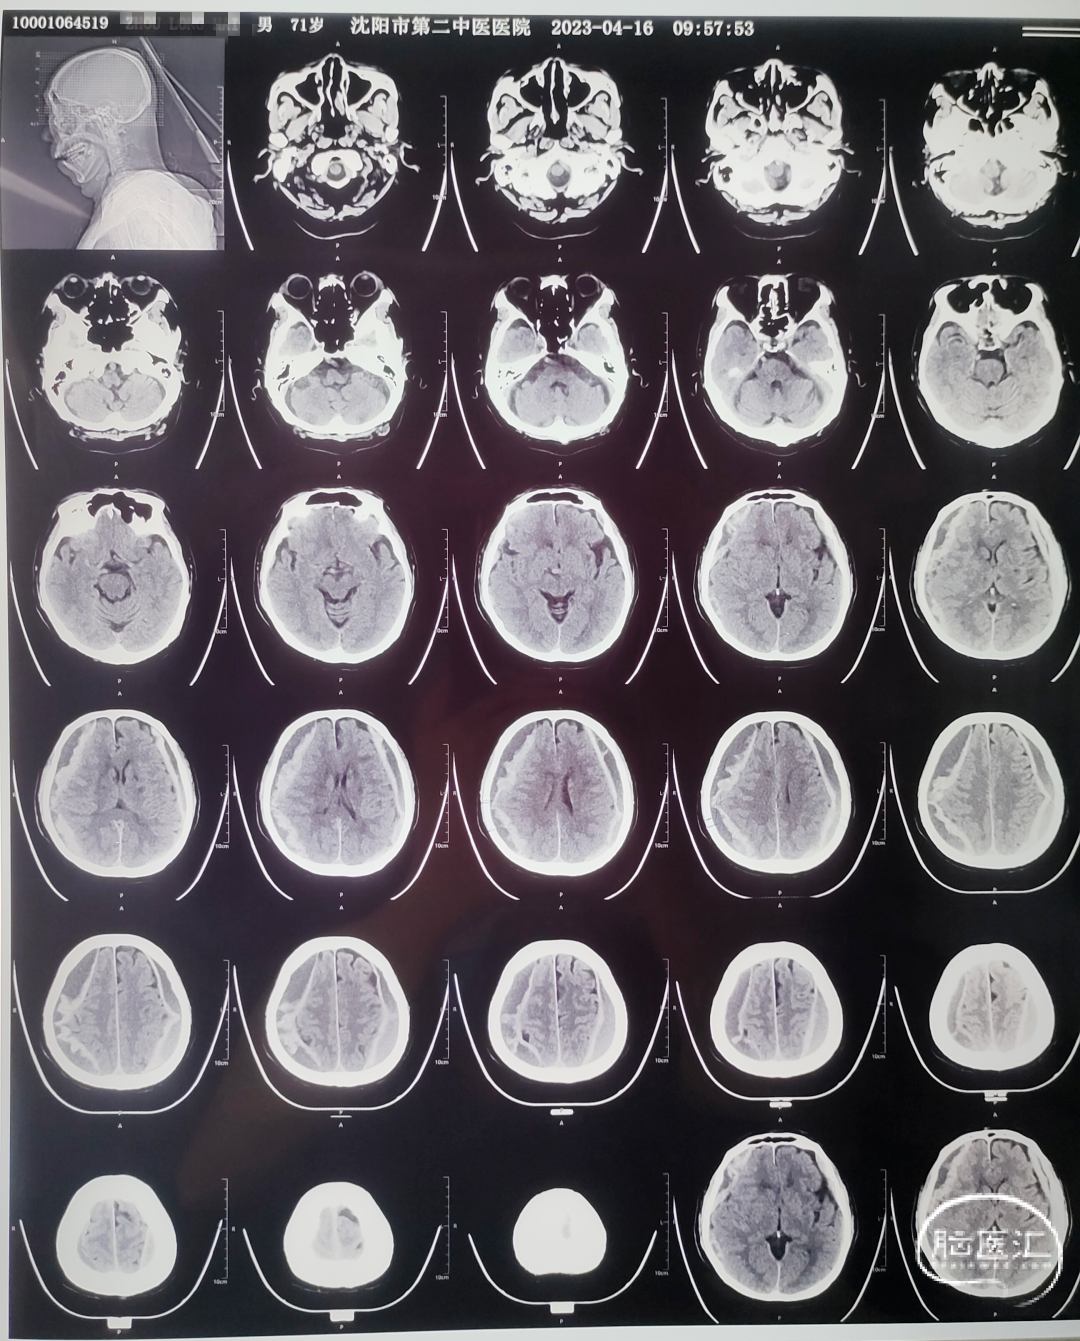

术前CT

患者颅内血肿混杂密度,考虑有急性血肿,予以神经内镜下血肿清除术。

术前术后对比